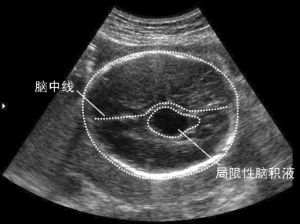

嬰兒腦積水的太難診斷,據其臨床由於表現,頭顱的快速增長及其特有的形態,推薦一般多無周四困難。成人腦積水的希望診斷則需依靠特殊的幾次檢查。頭顱透光試驗是對嬰兒腦積水一項最簡單而基本的檢查醫院。腦積水患兒整個頭顱都透光,僅在額頂部透光者常為硬膜下血腫或水瘤。頭顱超音波檢查腹腔,中線波不移位,常見擴大的腦室波。此項不配檢查對鑑別硬膜下血腫或水瘤頗有裨益。顱骨X線平片可見顱腔擴大,頭面比例不對稱,顱骨菲薄,顱縫分離,前後囟擴大,蝶鞍加深等改變。前囟穿刺(兩側側角入路)是診斷出來腦積水的一項簡單的方法,此法還能提示大腦皮質厚度,但做的不能說明腦積水系交通性或非交通性。這點可通過腦室及腰椎雙重穿刺和腦脊液酚紅或放射性核素試驗來鑑別。腦血管造影、腦室造影、CT及磁共振效果檢查均有助於診斷幾次,尤說話以後二項無創早上檢查最為實用,若系非交通性腦積水,尚可借這些中飯檢查找到梗阻部位及查明病變性質。